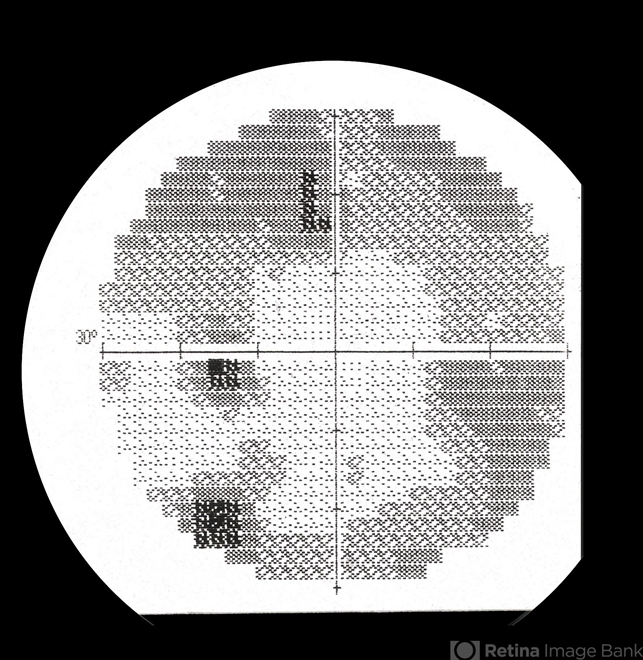

- syphilitic optic neuritis, acute humphry VF, scotoma

- Syphilitic optic neuritis, acute Humphry VF, scotomas.